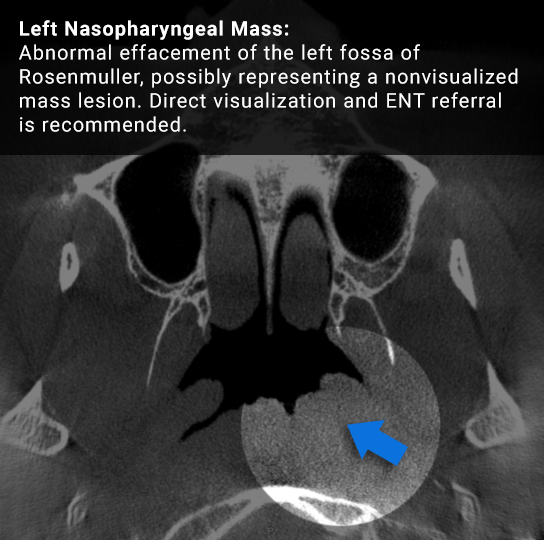

Can you identify the pathologies in the images below?

Image of an actual study taken from a CBCT machine Image of an actual study taken from a CBCT machine with the associated finding labeled on it

Drag the arrows to view the findings on the above scans.